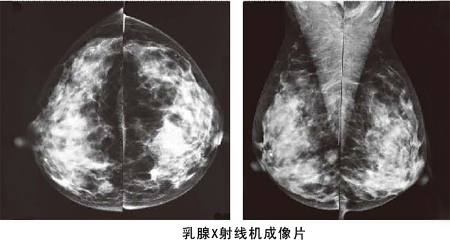

什么人適合做鉬鈀檢查?做乳腺鉬靶檢查有什么優(yōu)勢?

鉬靶和彩超是乳腺檢查中極常用的兩種檢查。那什么人適合做鉬鈀檢查呢?35歲以下醫(yī)生一般不推薦做乳腺鉬靶檢查,只需做彩超檢查即可。如超聲懷疑有問題,可再做鉬靶檢查。而鉬靶檢查是x射線檢查,所以我們女性懷孕前后建議不要做。40歲以上女性,因為進(jìn)入到乳腺癌高發(fā)年齡段,因此建議每年做一次鉬靶檢查。

做乳腺鉬靶檢查有什么優(yōu)勢?

乳腺鉬靶檢查是針對彩超檢查不能確定的腫塊,或是是不能發(fā)現(xiàn)的腫塊進(jìn)行檢查, 它的特點是可以檢測出醫(yī)生觸摸不到的乳腺腫塊,特別是對于大乳房和脂肪型乳房,其診斷性可高達(dá)95%,對于以少許微小鈣化為獨有表現(xiàn)的T0期乳腺癌,也只有憑借軟X線檢查才能被早期發(fā)現(xiàn)和診斷。

乳腺鉬靶檢查系統(tǒng)是一種低劑量乳腺X光拍攝乳房的技術(shù),它能清晰顯示乳腺各層組織,可以發(fā)現(xiàn)乳腺增生,各種良惡性腫廇以及乳腺組織結(jié)構(gòu)紊亂,可觀察到小于0.1毫米的微小鈣化點及鈣化簇,是早期發(fā)現(xiàn),診斷乳腺癌的極有效和可靠的方式,尤其對于臨床不可能及的,以微小鈣化簇為獨有表現(xiàn)的早期乳腺癌具有特征性的診斷意義。

乳腺鉬靶檢查系統(tǒng)具有成像清晰、檢查操作方便快捷、輻射量小等特點,該儀器檢查診斷可準(zhǔn)確發(fā)現(xiàn)乳腺增生、病變、包塊、鈣化的形狀、大小、密度、性質(zhì)等。對于彩超無法辨別的乳腺病變鈣化點進(jìn)行準(zhǔn)確判斷與鑒別。

另外鉬靶照相對于年輕女性乳腺有一定的損傷,因此檢查不宜過勤,40歲以上的女性一年檢查一次為宜。希望小編的這篇什么人適合做鉬鈀檢查以及做乳腺鉬靶檢查有什么優(yōu)勢的小文章能幫到大家。